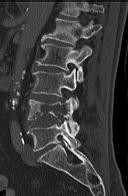

Figures 1 and 2 are CT scans obtained from a 68-year-old man who has had

progressive neck pain and stiffness, worsening gait imbalance, upper extremity weakness, early muscle fatigue, difficulty with fine motor control, and difficulty with activities of daily living over the past few years. On physical examination, he has a wide based stiff legged gait, generalized upper extremity weakness, dense sensory loss in the upper and lower extremities, and markedly brisk reflexes. What is the most appropriate treatment for this patient?

4. Posterior cervical laminoplasties from C3-6 Discussions: D

This patient has progressive myelopathy secondary to ossification of the posterior longitudinal ligament. Diagnostic imaging reveals multilevel cervical cord compression from C4-6. The patient has maintained reasonable cervical lordosis. A posterior procedure such as multilevel laminoplasty

decompresses the spine, is motion preserving, and has a low complication rate. Observation and cervical epidural injections are not viable options in patients with progressive myelopathy. Anterior cervical decompression, including corpectomy, is an option; however, anterior procedures have an increased risk of complications such as dural tear or cerebrospinal fluid leak. The axial CT image shows a "double layer" sign, which is consistent with dural ossification and increases the risk of dural injury with anterior decompression